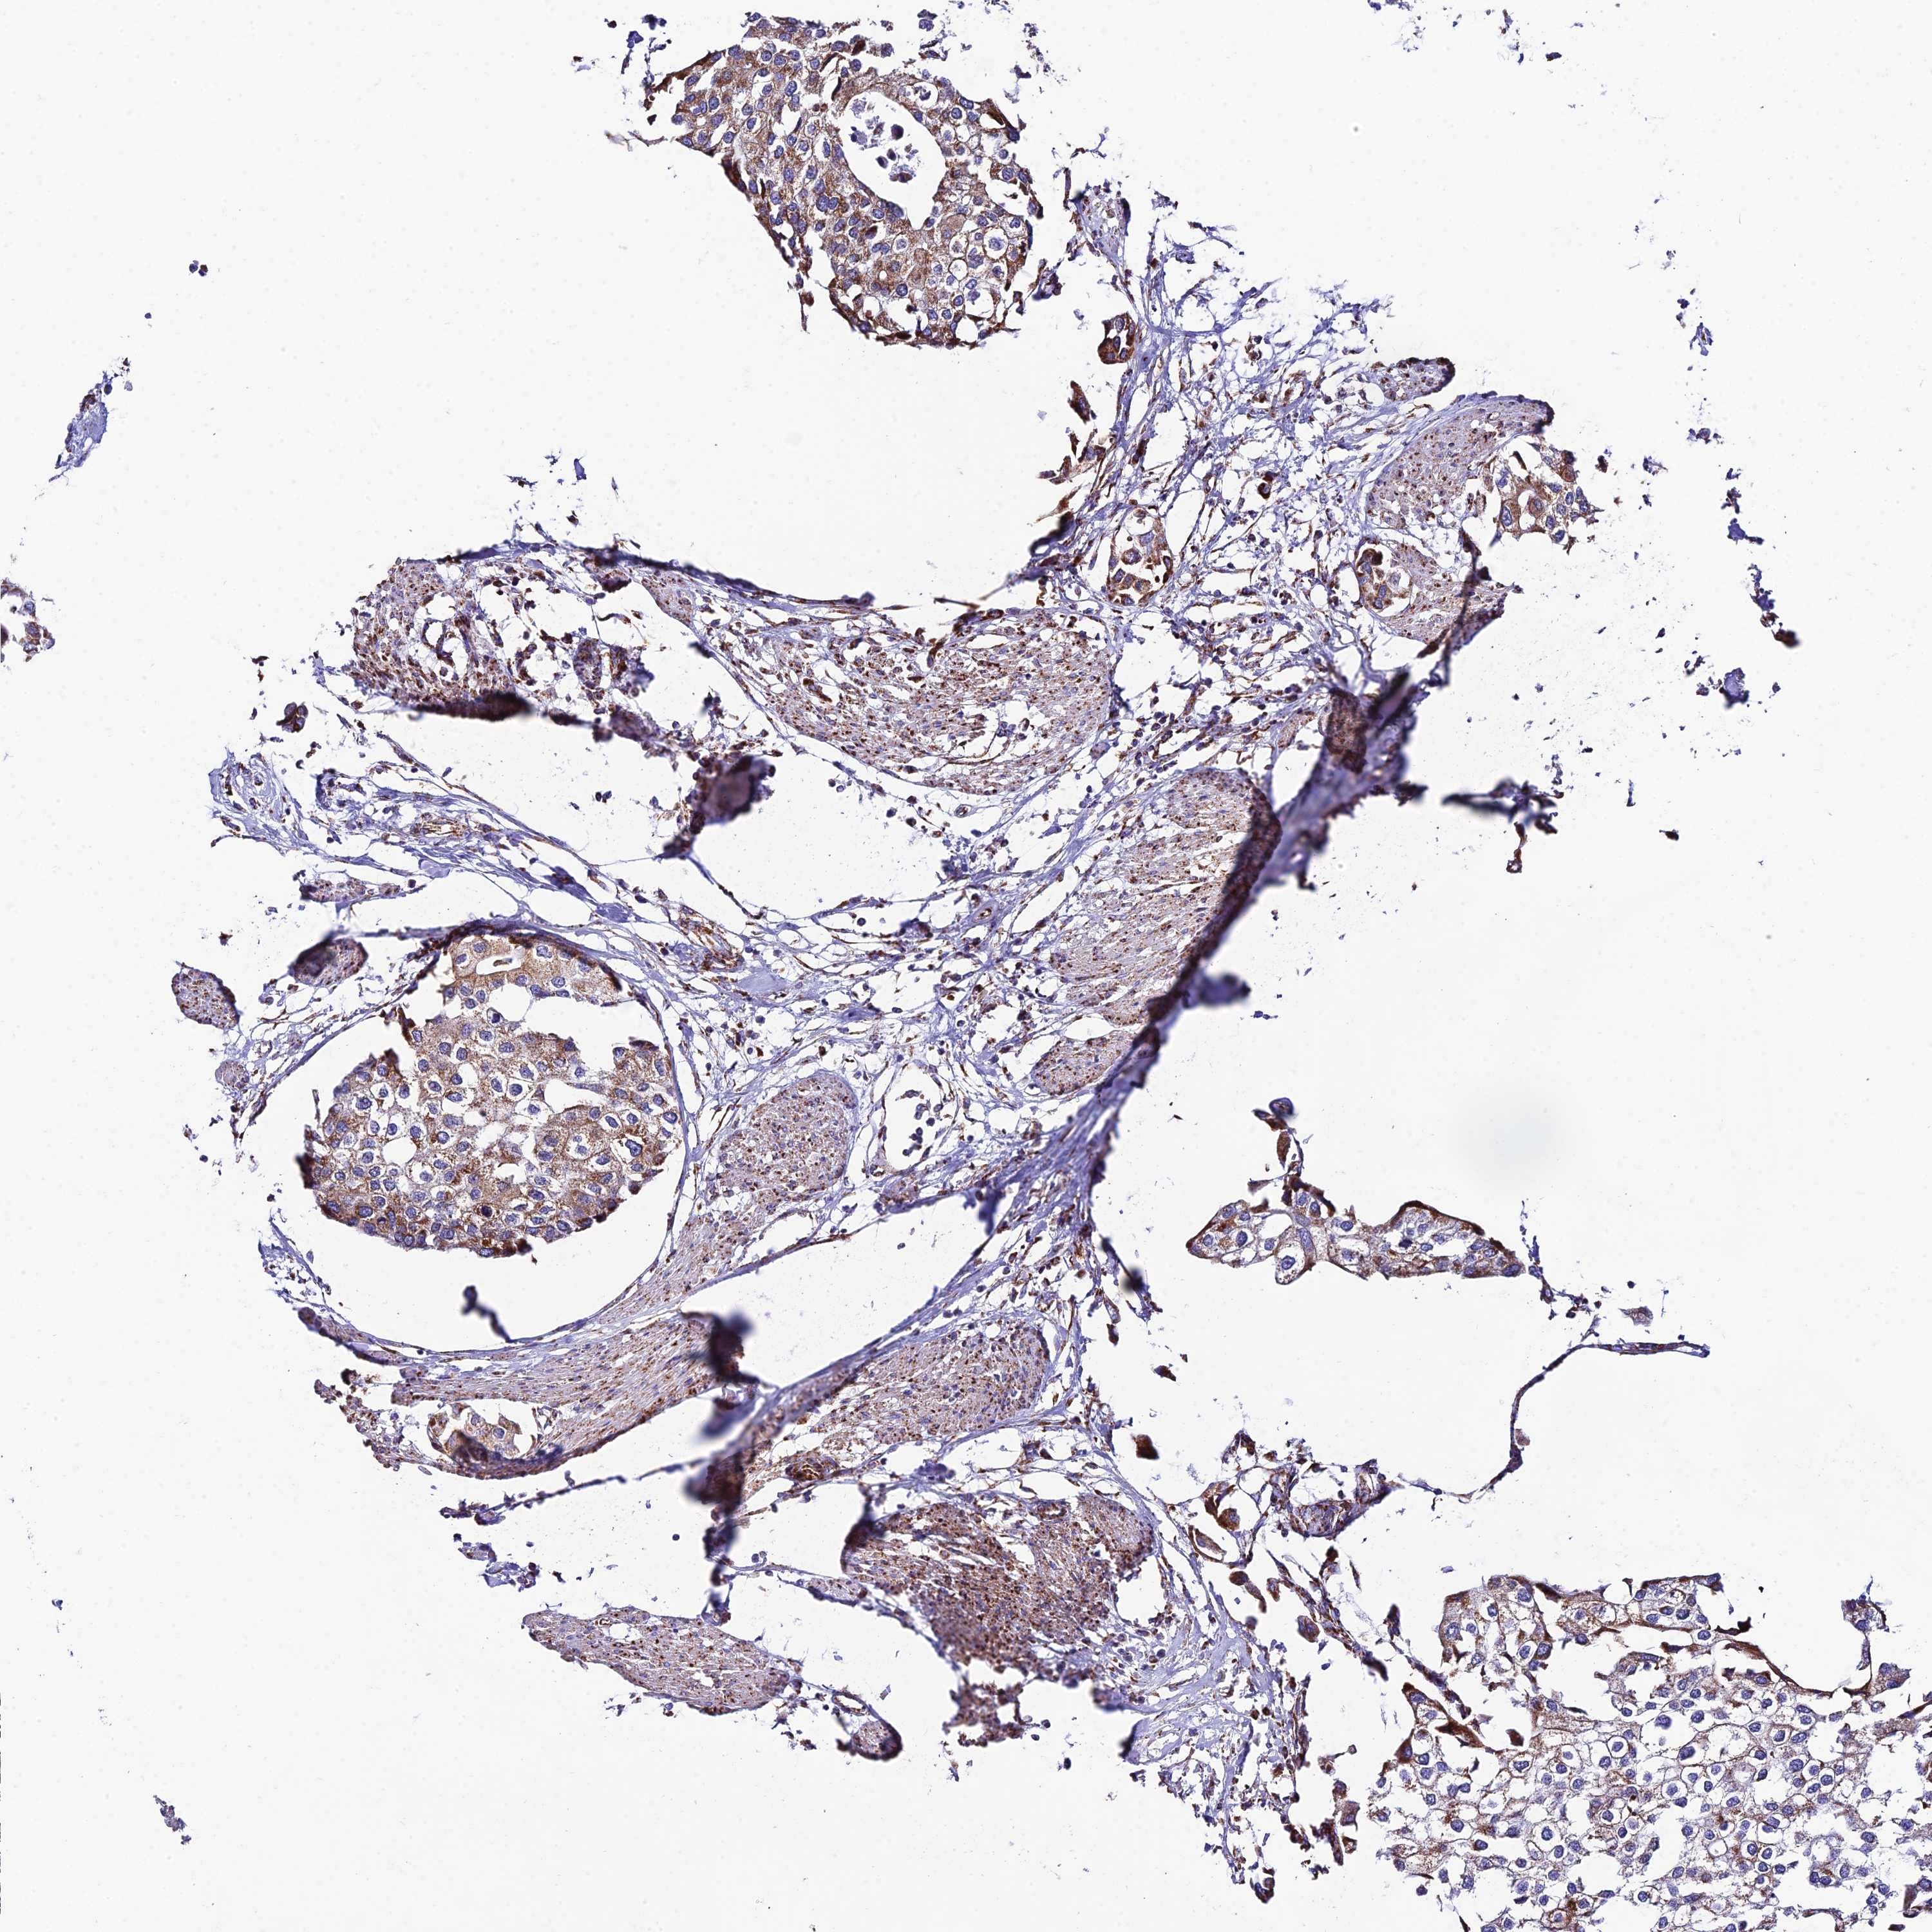

UROTHELIAL CANCER - Protein expressioni

A mouse-over function shows sample information and annotation data. Click on an image to view it in a full screen mode. Samples can be filtered based on level of antibody staining by selecting one or several of the following categories: high, medium, low and not detected. The assay and annotation is described here.

Note that samples used for immunohistochemistry by the Human Protein Atlas do not correspond to samples in the TCGA dataset.

Antibody stainingi

Antibody staining in the annotated cell types in the current human tissue is reported as not detected, low, medium, or high, based on conventional immunohistochemistry profiling in selected tissues. This score is based on the combination of the staining intensity and fraction of stained cells.

Each image is clickable and will lead to virtual microscopy that enables deeper exploration of all samples and also displays staining intensity scores, fraction scores and subcellular localization as well as patient and tissue information for each sample.

Antibody HPA042935

Staining

High

Medium

Low

Not detected

Intensity

Strong

Moderate

Weak

Negative

Quantity

>75%

75%-25%

<25%

None

Location

Urothelial carcinoma, High grade

Urothelial carcinoma, Low grade

Urothelial carcinoma, NOS